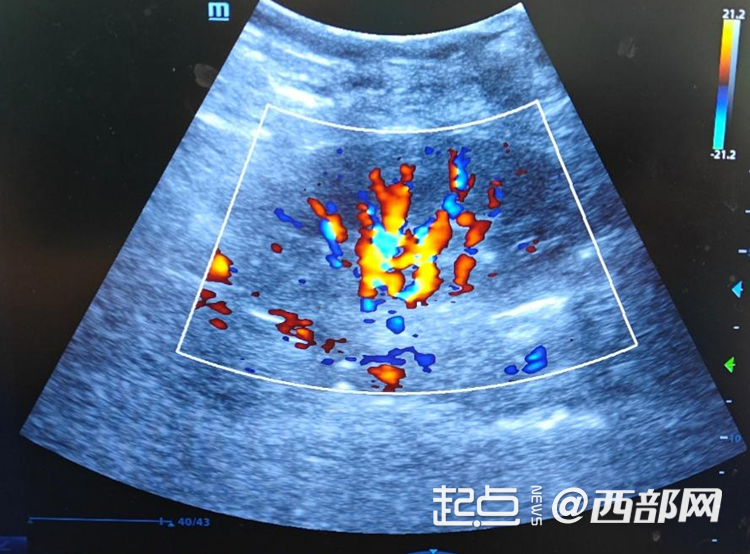

移植肾血流超声

经过严谨的术前评估、周密的准备以及高效的伦理审批流程,手术如期开展。术中,西京医院泌尿外科肾移植团队凭借丰富的临床经验和精湛的技术,精准完成血管吻合等关键操作,整个过程顺利流畅,开放血流后移植肾即刻恢复功能并产生尿液。